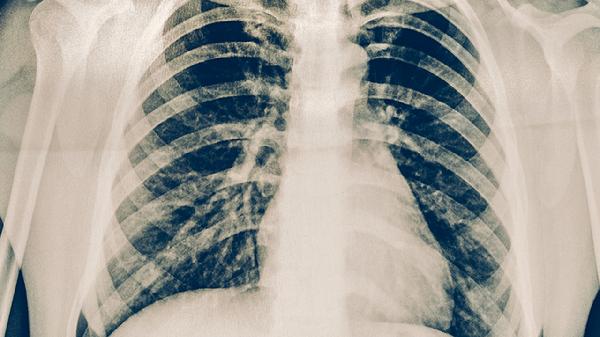

肺结核治疗药物如异烟肼片、利福平胶囊等可能对生殖细胞或胎儿发育产生影响,停药后需等待药物完全代谢。抗结核药物半衰期较长,部分成分可能在体内残留数月,过早怀孕可能增加胎儿畸形或发育异常的风险。患者需完成全程规范治疗并复查痰培养、胸部CT等确认病灶稳定,确保无活动性结核杆菌残留。若合并肝肾功能损伤,需延长等待期至肝功能指标恢复正常。医生会根据个体情况调整备孕时间,期间建议采取可靠避孕措施。

备孕前应进行结核菌素试验、胸部影像学复查,排除复发可能。女性需补充叶酸片预防神经管缺陷,男性应避免吸烟饮酒。妊娠期间若出现低热、咳嗽等症状需及时排查结核复发。哺乳期患者需告知医生用药史,避免通过乳汁传递药物成分。定期监测母婴健康状况,必要时在感染科与产科联合指导下进行干预。